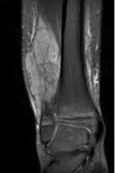

Se usa una amplia gama de técnicas de adquisición de imágenes para poder ver dentro del cuerpo y determinar el alcance de un sarcoma óseo y establecer la presencia o ausencia de enfermedad metastásica distante.

2. Resonancia magnética

Pruebas de imágen

Las pruebas de diagnóstico por imágenes utilizan ondas sonoras, rayos X, campos magnéticos o sustancias radiactivas para crear imágenes del interior del cuerpo. Las pruebas de diagnóstico por imágenes pueden realizarse por diversos motivos, como:

Las imágenes más representativas o más comunes son:

5. Resonancia Magnética